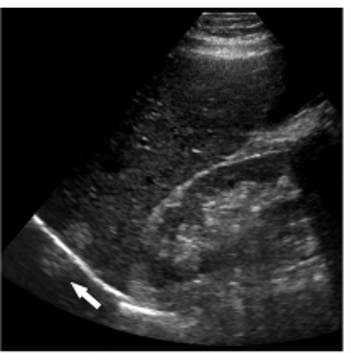

why do you get a tapering triangle in comet tail artifact?

comet tail artifact is a form of reverberation, but the two parallel highly reflective surfaces are closer together –> sequential echoes are closely spaced

spce between reflectors may be < SPL (minimal distance needed for axial res)

Reason you see a triangle and not a square: later echoes get attenuated and have decreased amplitutde. Decreased amplitude is manifested on the displayu as decreased width. So you get a tapering triangle